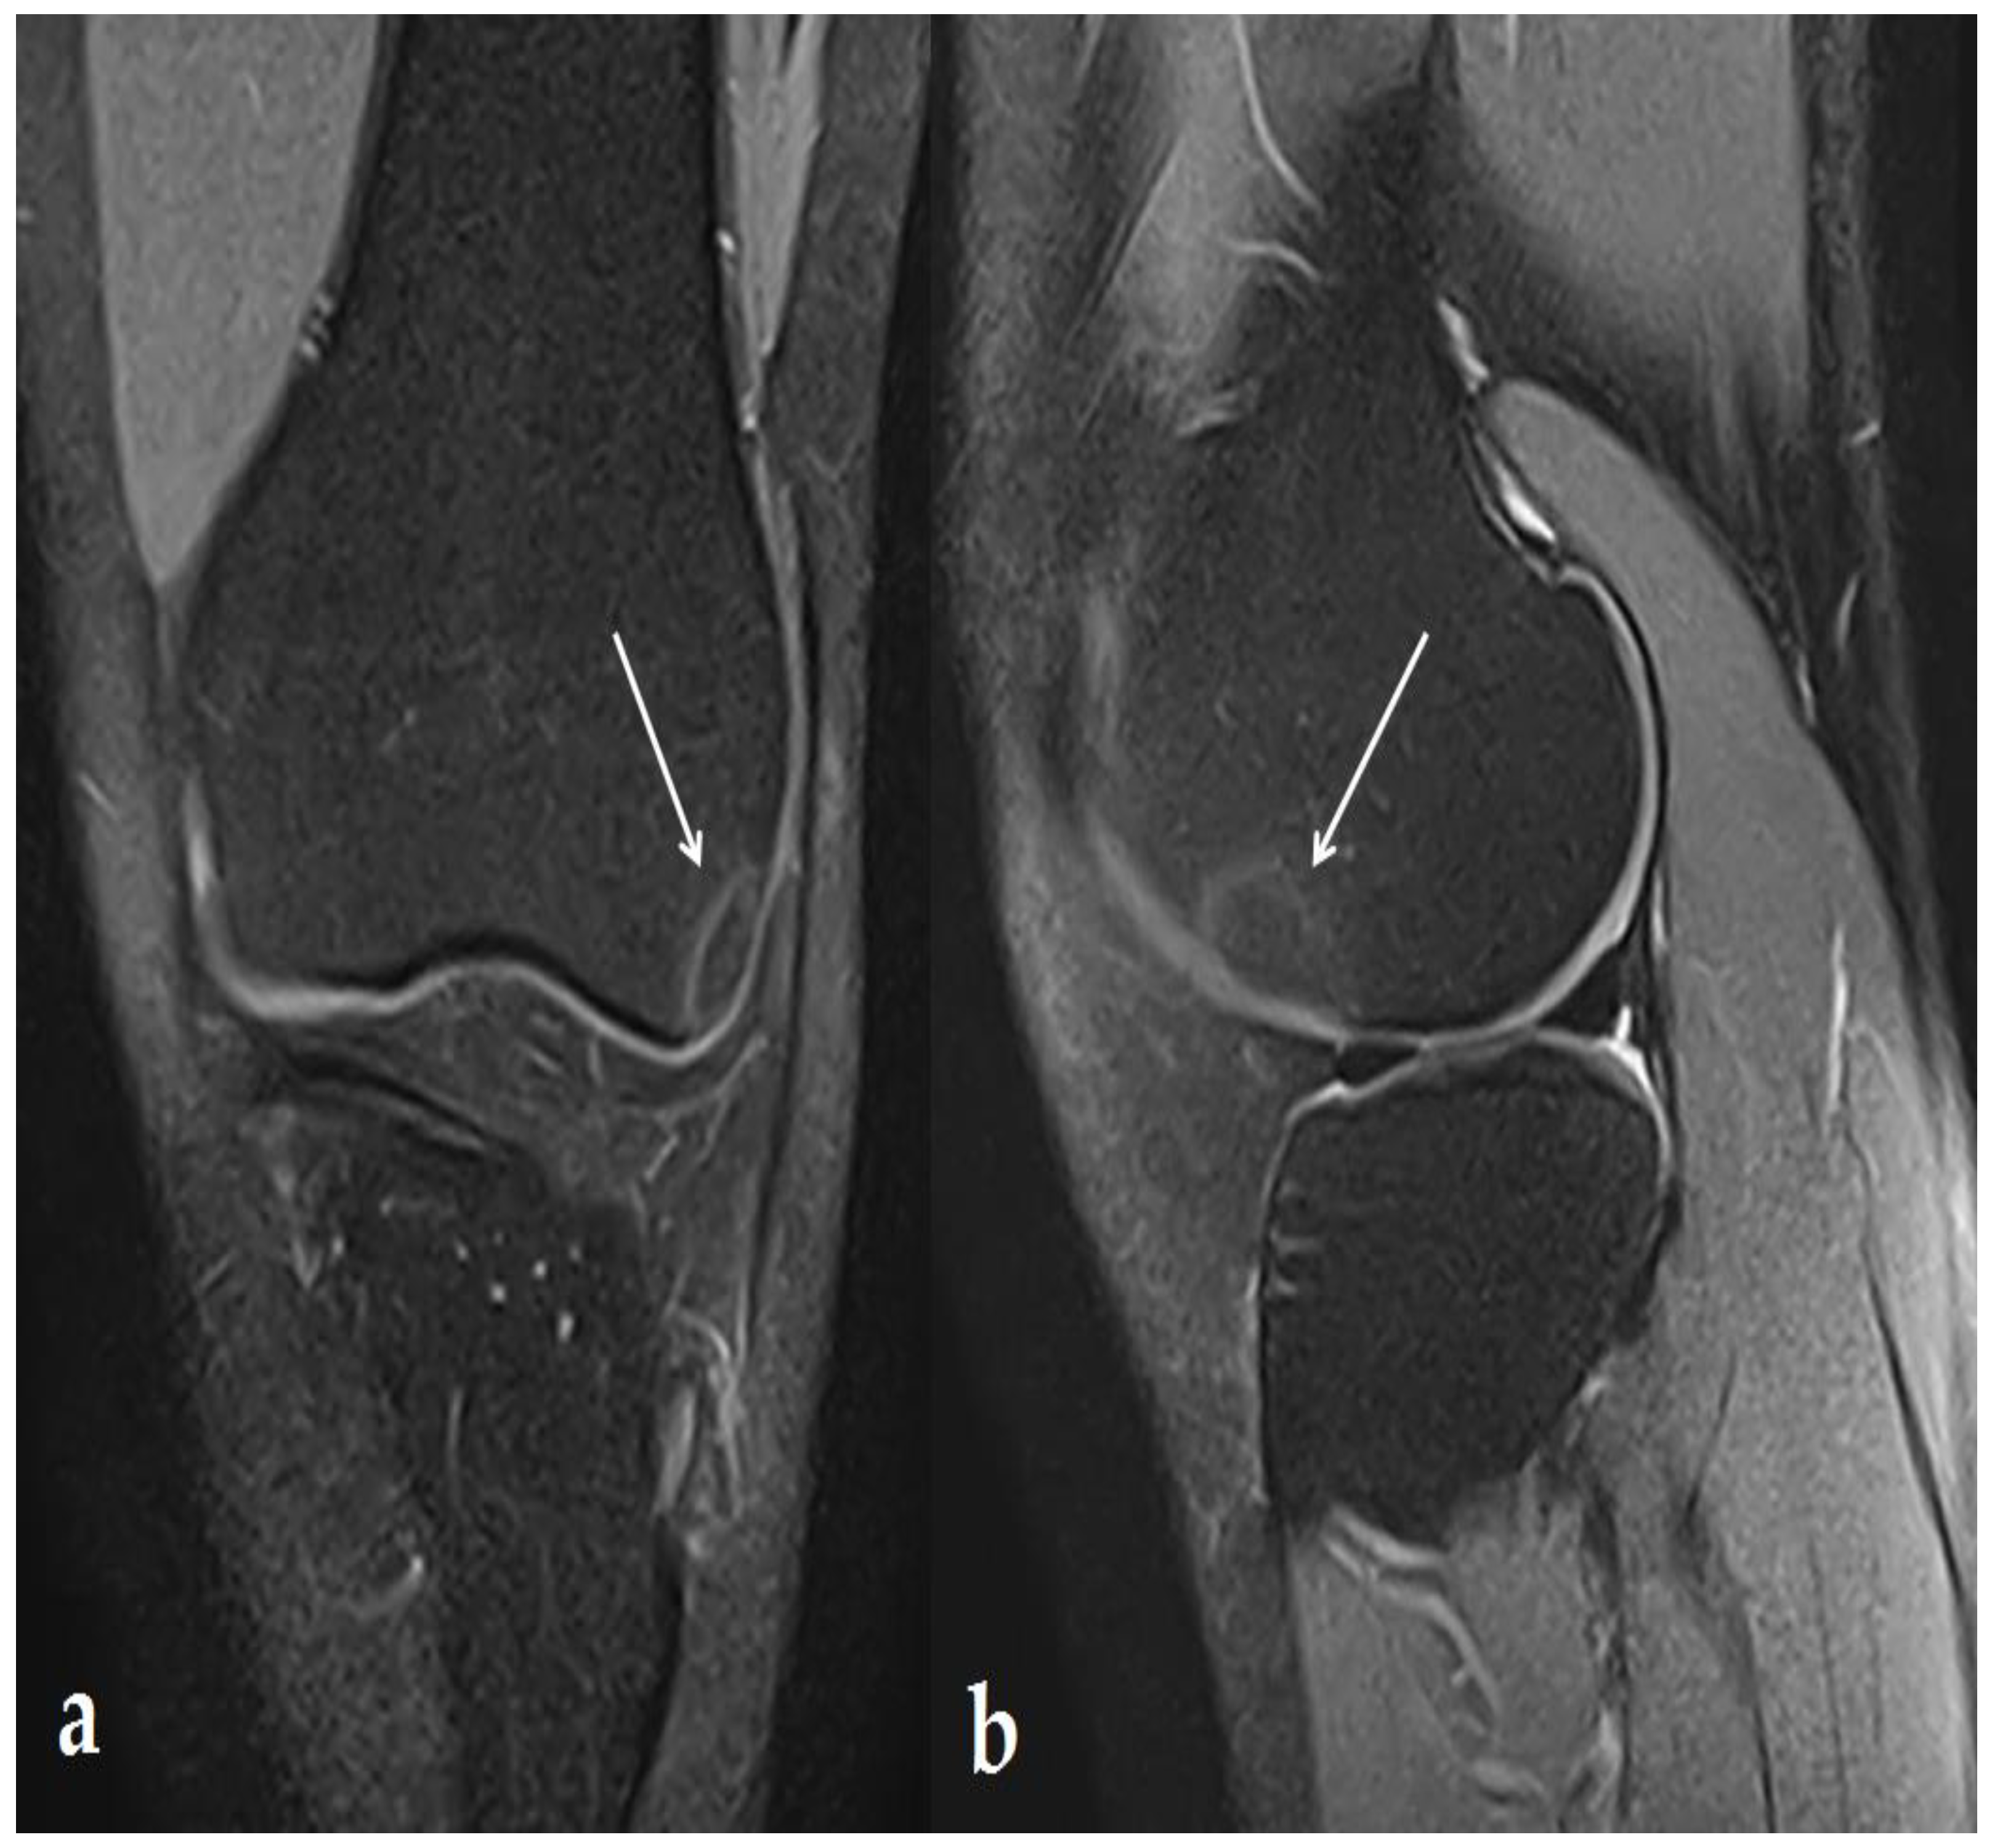

2. Case Report

3.1. Knee Lesions Encountered

3.1.2. Osteonecrosis Lesions of the Knee